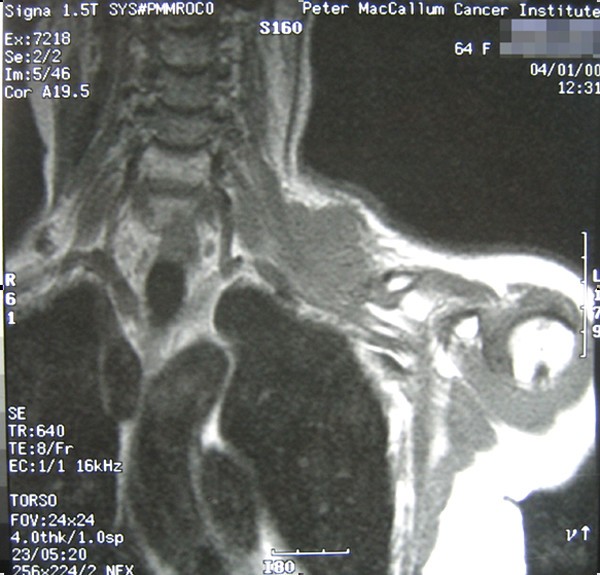

She re-presented in December 1999 with a mass in the left supraclavicular fossa and numbness in the arm, but no motor weakness. The mass was located within the area previously irradiated to 60 Gy. Her disease was staged with our standard protocol at the time with MRI of the neck and shoulder, CT of the chest and functional imaging using thallium-201 scintigraphy [10]. MRI showed a 3 cm × 5 cm mass involving the brachial plexus (Figure 1). Open biopsy confirmed pleomorphic spindle cell sarcoma.

The management of her case was discussed in our multi-disciplinary meeting. The agreed treatment plan was preoperative radiotherapy followed by en bloc resection. She received an accelerated hyperfractionated course of radiotherapy 48 Gy in 40 fractions (ICRU-50), treating twice a day over four weeks. The radiation field incorporated the brachial plexus and used 6 MV photons in an anterior-weighted, opposed oblique arrangement avoiding the spinal cord. Radiotherapy was completed in February 2000. Restaging investigations showed that the lesion had become more cystic on MRI, but its size had not changed. The degree of thallium-201 scintigraphy uptake had not changed significantly either. The patient proceeded on to surgery four weeks later.